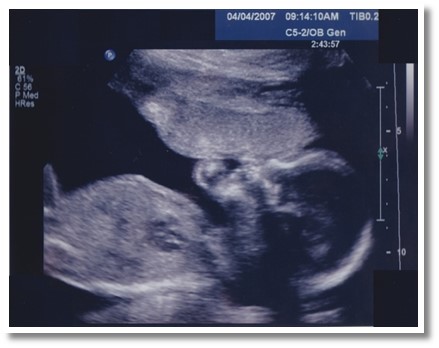

Baby Chris is 15 Weeks Old

Fifteen weeks after conception (17 weeks LMP), Baby Chris is five inches long and weighs five ounces—about the size of a turnip.

Stem cells are multiplying in the bone marrow. Baby Chris’s sweat glands are starting to develop. In the respiratory system, the bronchial tree is almost complete and the airways contain smooth muscle and nerve bundles.